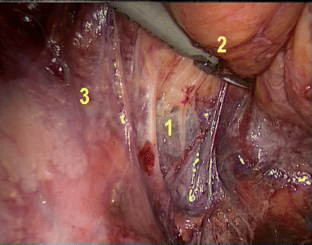

The key steps are: preparation of the splanchnic nerves at the mid-posterior sidewall, the hypogastric nerves at the upper sidewall, and the urogenital nerve branches (Walsh) at the caudal-anterior sidewall. The dissection of the lateral ligament is strictly performed as the last step. NOME was applied in 274 consecutive mesorectal excisions (partial 20.4 %, total 79.6 %); a subgroup of 42 male patients underwent a questionnaire-based interview on sexual activity.